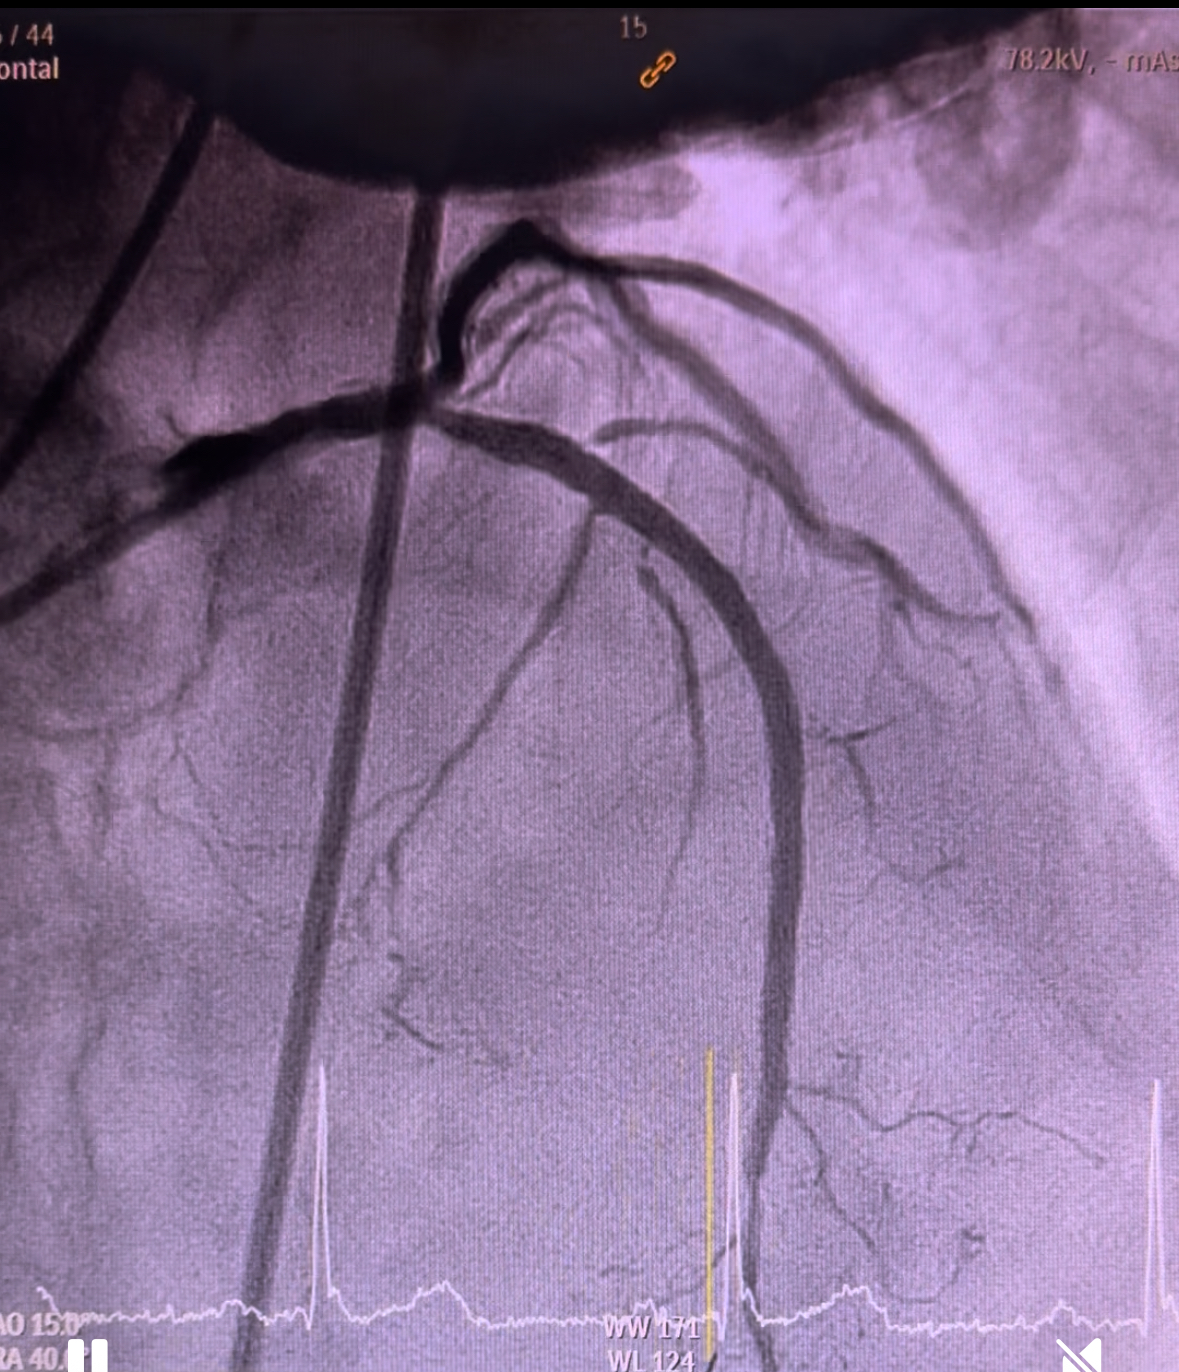

Coronary angiogram demonstrated smooth left main, 90% stenosis in the proximal left circumflex, 99% focal stenosis with severe calcification at mid LAD, followed by mild diffuse plaque until the distal end, and 90% stenosis at ostial D1. Right coronary was calcified with 80% stenosis at the proximal segment, 90% stenosis at the mid segment, and CTO at the distal segment. Discussion was held with cardiothoracic surgeons in which CABG was viewed incompatible.